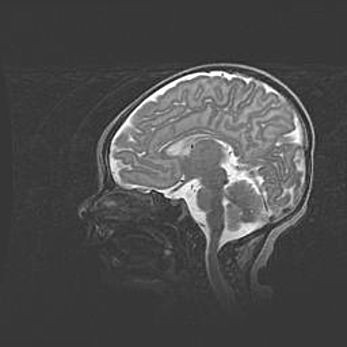

Аномалия Денди-Уокера. Признаки гипоплазии мозолистого тела.

Возраст: 5 месяцев 3 дня

Вес: 5550 г

Пол: мужской

Окружность головы: 39 см

Срок гестации: 40 недель

Аномалия Денди-Уокера – это порок развития головного мозга, для которого характерна триада симптомов: гипотрофия или аплазия червя мозжечка и/или полушарий мозжечка, расширение четвёртого желудочка с формированием ликворной кисты задней черепной ямки, гипертензионная гидроцефалия различной степени.

Гипоплазия мозолистого тела относится к дефектам внутриутробного этапа развития мозговой ткани, возникающим в процессе закладки структур головного мозга, что происходит на начальных этапах развития эмбриона.